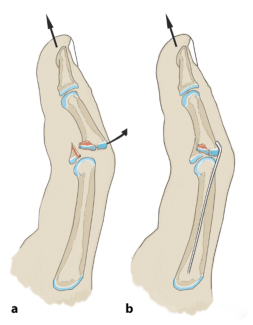

1. Схема модели чрескожной операции по уменьшению и фиксации стальными штифтами:

Применяют методику репозиции Хинтрингера и Эндера: сжатый костный фрагмент удаляют из костномозговой полости через дорсальное костное окно. Потяните вперед и согните проксимальный межфаланговый сустав на 20–30 градусов, чтобы уменьшить подвывих. Зафиксируйте костный фрагмент и проверьте устойчивость пальца в разогнутом положении. Если сохраняется тыльный подвывих средней фаланги, необходимо также заблокировать шкив, в котором в фалангу вводится стальной штифт.

1) Перелом I типа основания средней фаланги.

Разрез производят дорсально от средней фаланги в сухожильном треугольнике. При продольном вытяжении (стрелка) палец сгибается на 20–30°. Просверлите отверстие через разрез, наклонив его проксимально (изображение ниже).

Согните один конец 1-миллиметровой проволоки на 30°, чтобы придать ей форму хоккейной клюшки. Затем его вводят в костномозговую полость через просверленное отверстие.

Сокращение суставной поверхности и подвывих при вытяжении. Изогнутая проволока занимает примерно четверть площади соединения. Проксимальная суставная поверхность играет здесь вспомогательную роль.